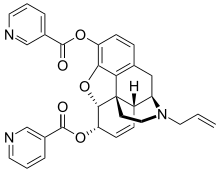

Nicomorphine Nicomorphine | ||

- Nicomorphine